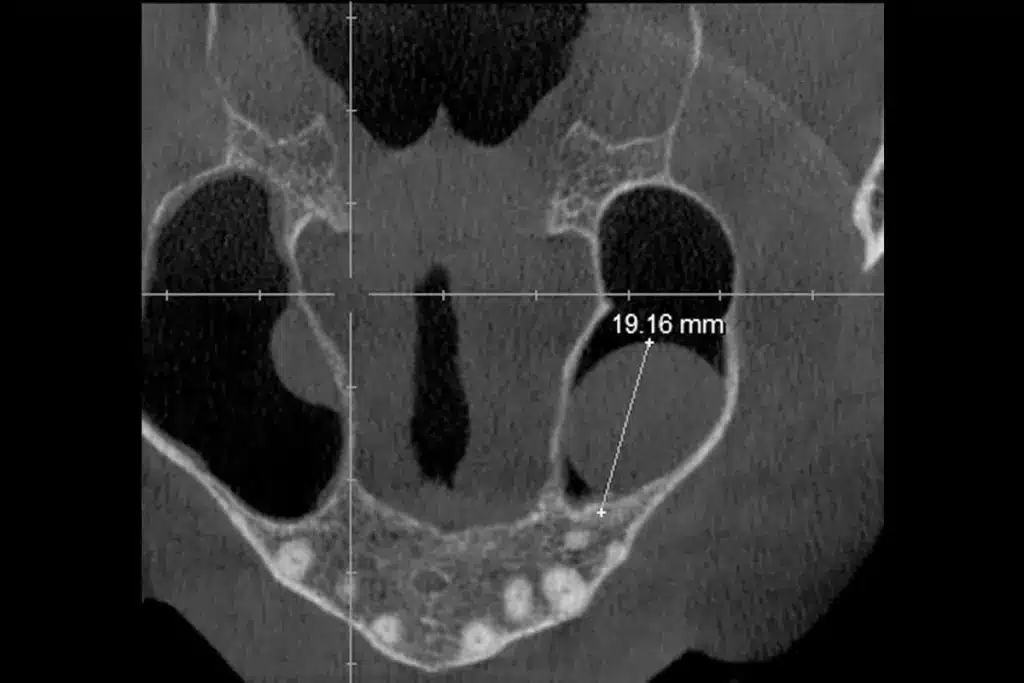

Imaging Studies

When complications are suspected or the diagnosis is unclear, imaging studies are used. Techniques like CT scans or MRI give detailed images of the ear and surrounding areas. They help assess the infection’s extent and its impact on nearby areas, including the brain.

Understanding the extent of an ear infection is vital. It helps determine the right treatment plan. This way, we can avoid long-term effects, such as ear infection brain damage.